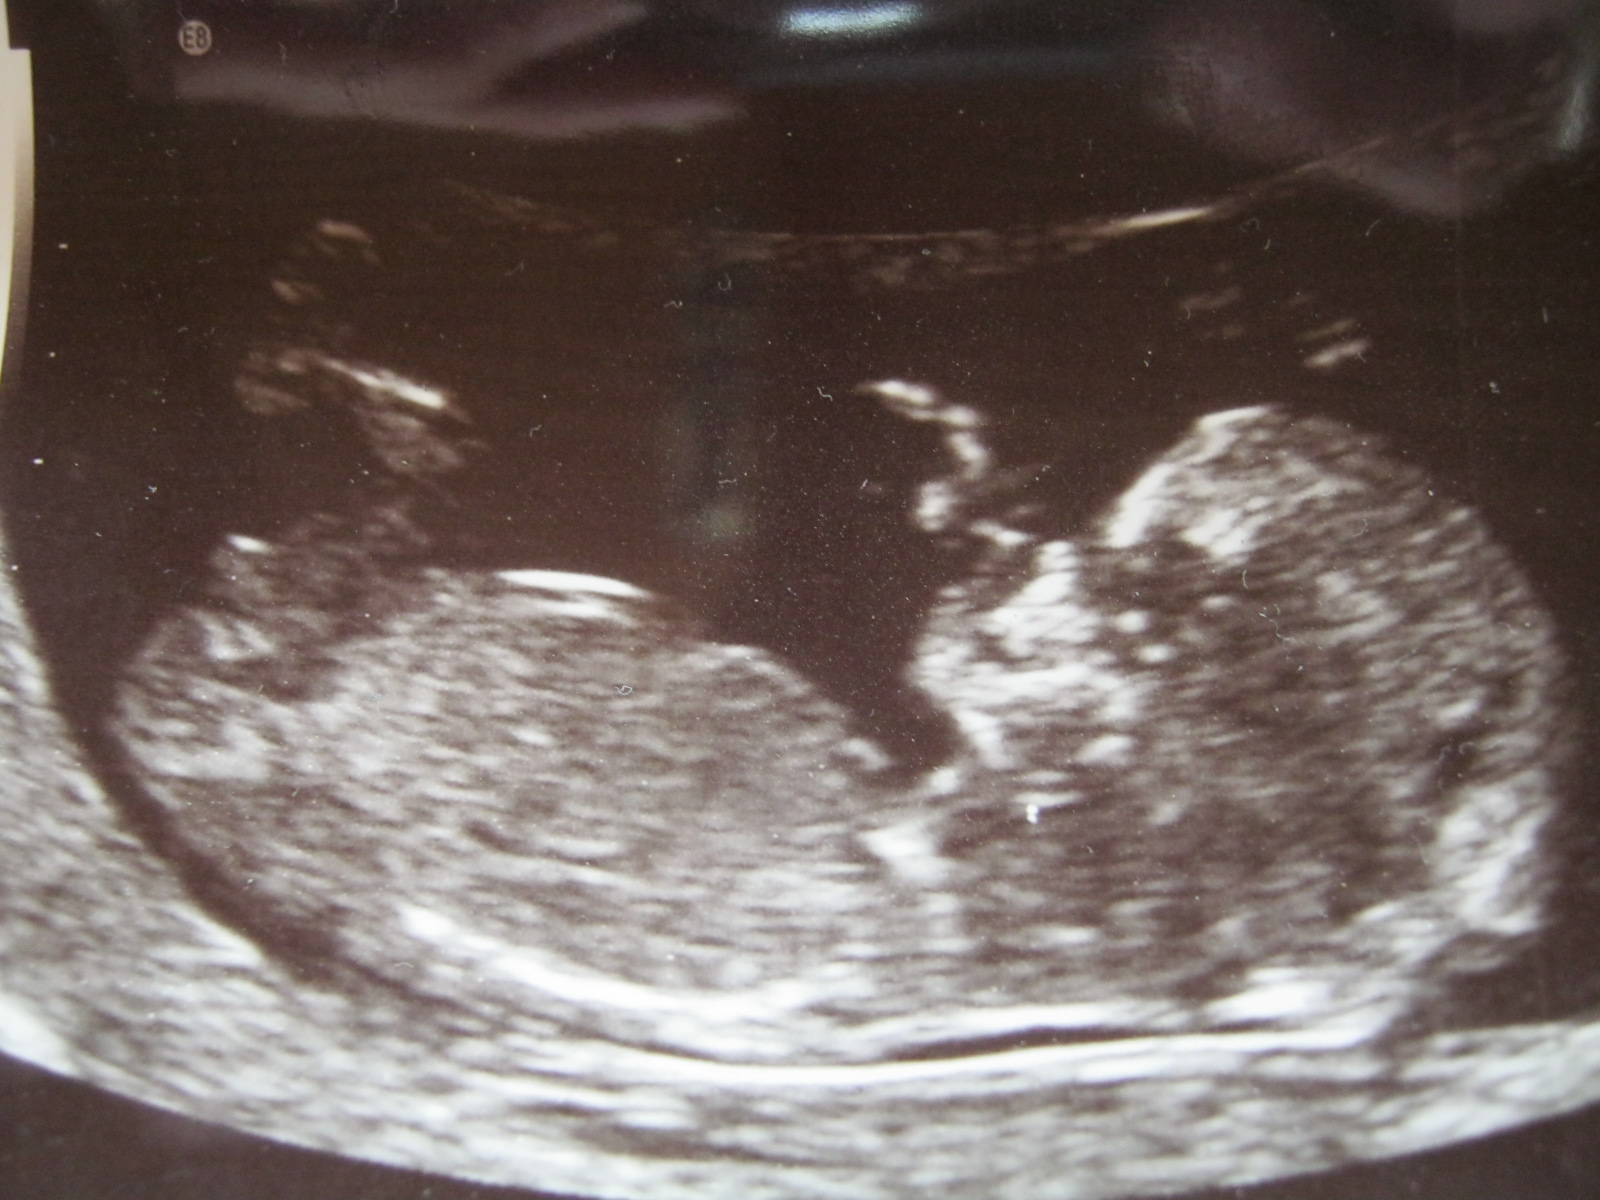

What do you think. Scans were at 12w 3 days.Attachment 2900Attachment 2901Attachment 2902

I can't see a nub. Cute baby tho! :)

Ditto - no nub seen

I see a nub...but no clue. Looks more girl than boy to me....I'm no expert though :(

It's "busy" down there which would make me lean boy (not an expert). Did you see any more clues in your ultrasound??

Well i could see the nub clearly sticking out but i was trying really hard to focus on the head end so as to not ruin the suprise if that makes sense. With my last son it was much higher and so clearly a boy. This time i think boy again as it seemed to have a definate angle but i was trying not to lose my hope of it being a girl so was therefore not looking right at it.